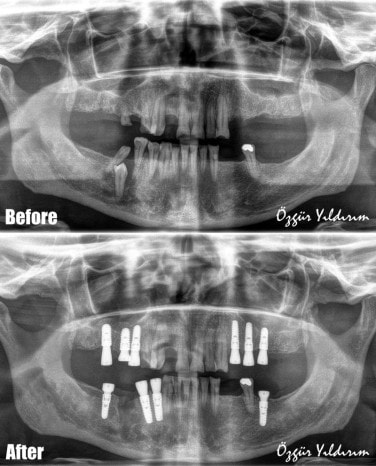

Зубные имплантаты All-On-6 - это популярное стоматологическое лечение, предлагающее постоянное решение проблемы отсутствующих зубов. Процедура включает в себя установку шести титанных имплантатов в каждую челюсть, на которые затем крепится несъемный протез. В тот же день, когда устанавливаются имплантаты, пациент получает временный протез, обеспечивая сохранение функции зубов без перерыва.

Mastery Dental Clinic в Анталье предлагает профессиональные услуги по установке зубных имплантатов All-On-6. Доктор Özgür Yıldırım имеет многолетний опыт в проведении этой процедуры и использует современные технологии и материалы. Клиника обеспечивает комфортные условия, внимательный персонал и индивидуальный подход к каждому пациенту.